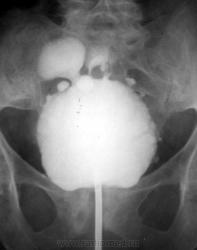

Архив. Выраженный хронический цистит. Цистография.

Из архива кафедры. Нечасто встретишь такое. Цистография. Фаза тугого заполнения и после микции.

Видел от силы 3, но чтобы такую "махровость" - никогда. Интересно, чем объяснить заброс контраста в дистальные отделы мочеточников после опорожнения?

А это не множественные дивертикулы?